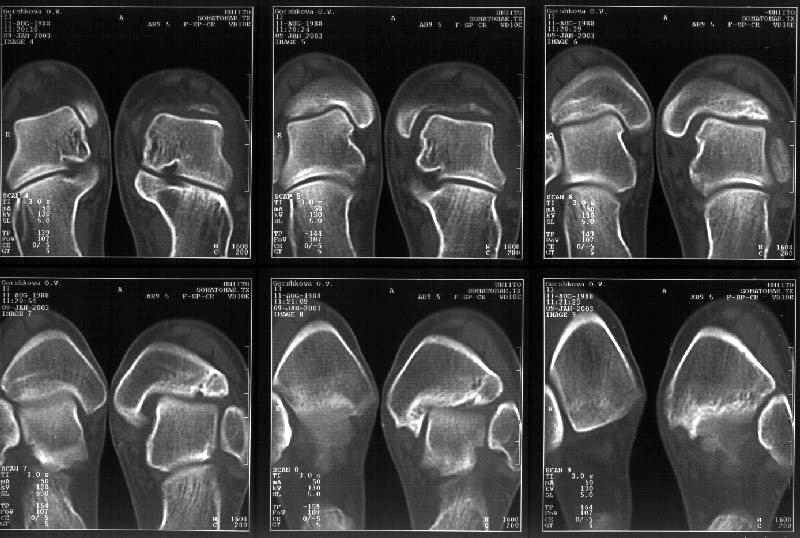

Мне в тоже время совершенно ясно видно по той же КТ, по 4 срезам, расположенным в центре и вверху пленки, что перелома внутренней лодыжки не было, в следующем собщении я приложу увеличенный фрагмент томограммы. А к этому письму прилагаю увеличеный фрагмент послеоперационной рентгенограммы, где выделил отколотый фрагмент

позади внутренней лодыжки. И он, как я вижу, находится между стержнем и тараном. А перелома внутренней лодыжки, и тем более смещения, IMHO

не определяется.

Отправитель: Alexander Chelnokov 12 Январь 2003, 14:55

> направлениях.Отдавил и отломал переднюю часть мед. маллеолюса от его

> тибиальной основы. По мне, КТ это совершенно ясно показывает.

Здесь 4 среза, начиная от основания лодыжки и проксимальнее. Где, по Вашему мнению, проходит линия перелома, отделяющая переднюю часть внутренней лодыжки от большеберцовой кости? Заранее спасибо.